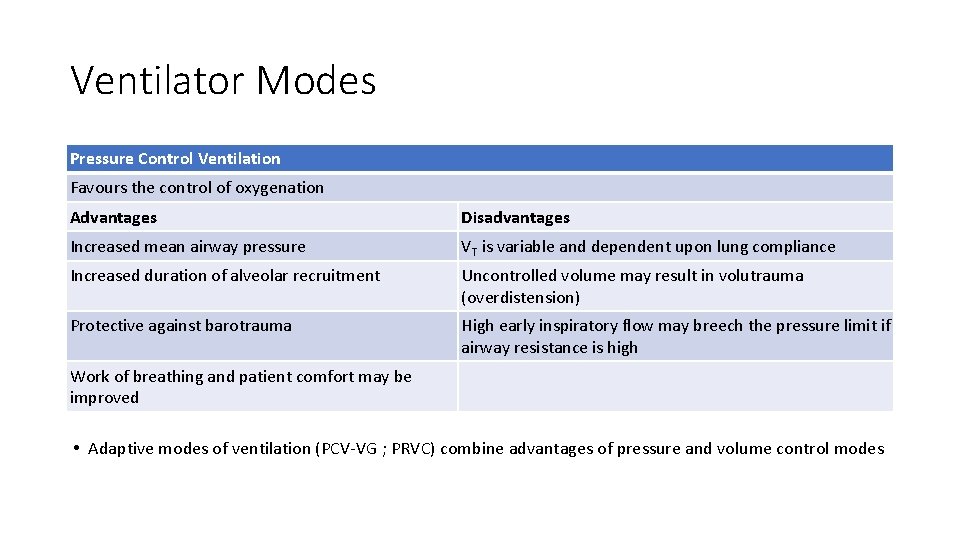

Ventilator Modes Pressure Control Ventilation Favours the control of oxygenation Advantages Disadvantages Increased mean airway pressure VT is variable and dependent upon lung compliance Increased duration of alveolar recruitment Uncontrolled volume may result in volutrauma (overdistension) Protective against barotrauma High early inspiratory flow may breech the pressure limit if airway resistance is high Work of breathing and patient comfort may be improved • Adaptive modes of ventilation (PCV-VG ; PRVC) combine advantages of pressure and volume control modes